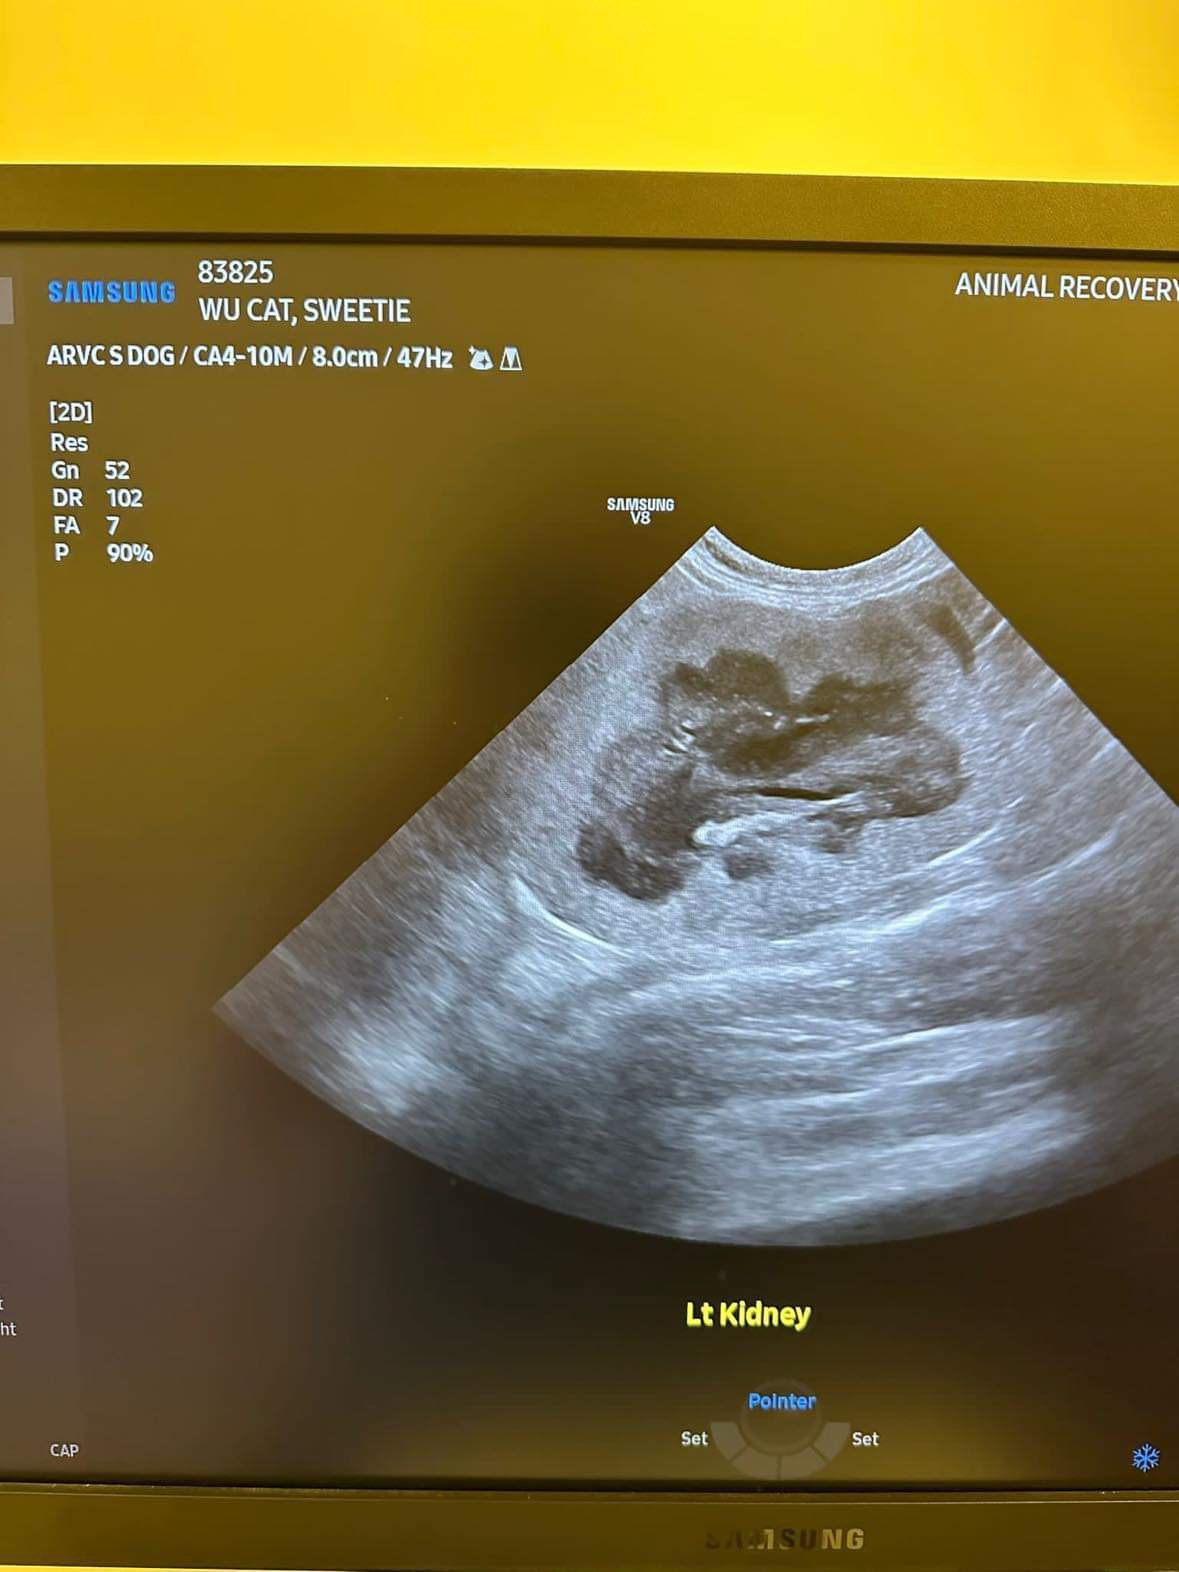

U/s done and basically not much use to me, liver got issue, kidneys got some fatty deposits which is diabetic, so insulin correct. Gall bladder got some obstruction so just start urofalk. All in must put o tube. Dr Daniel do it.

her left kidney 8.0cm, right 7.0cm also double the normal size

Dr ym scan sweeties, dr flo not involve, both got free fluid ard the kidneys, left kidney is extremely abnormal, right kidney abnormal.